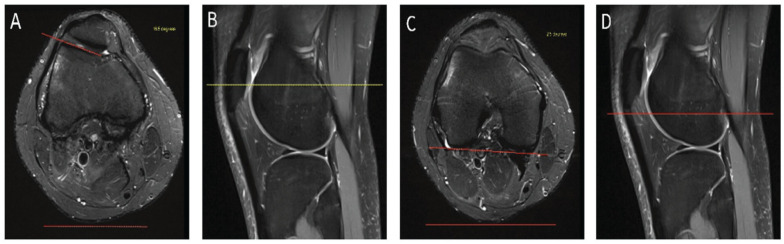

Methods: After institutional review board approval, medical records were retrospectively reviewed to form a PI group and a control (no PI) group. The 2-image LTI was first measured by 2 raters to determine intrarater and interrater reliability. A receiver operating characteristic curve was created to determine a diagnostic cut-off value. After applying this cutoff between the groups, the resultant sensitivity and specificity were calculated.

Results: The 2-image LTI measurements demonstrated excellent intrarater and interrater reliability. The PI group had a mean LTI of 2.58°, while the control group had a mean LTI of 17.26°. A diagnostic threshold LTI value of 13.7° was determined, discriminating between patients with and without recurrent PI due to trochlear dysplasia, with a sensitivity of 0.889 and a specificity of 0.780. The area under the curve was 0.887.